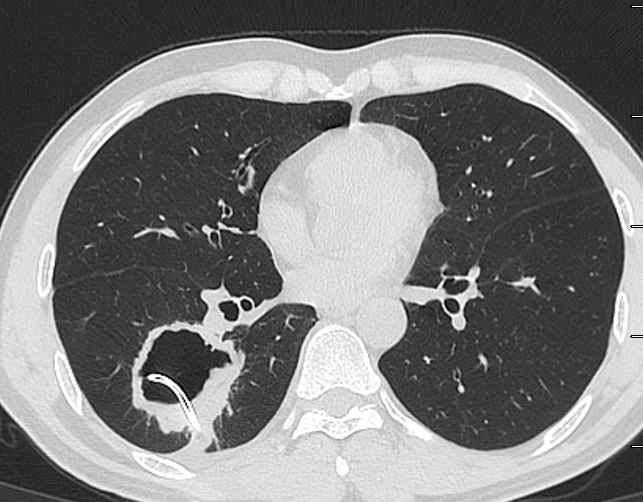

肺脓肿CT

内壁光滑均匀强化的肺脓肿,抗炎治疗12天明显好转——张军营,安阳市